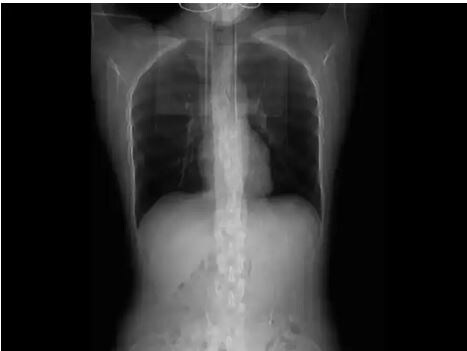

नवी दिल्ली, 21 डिसेंबर : एखादा मोठा अपघात झाला किंवा हाणामारीमध्ये मार लागल्याने बरगड्या मोडल्याचं तुम्ही अनेकदा ऐकलं असेल. परंतु, चीनमधल्या एका महिलेच्या बरगड्या मोडल्याचं कारण ऐकलंत तर तुम्हाला आश्चर्य वाटेल. तिखट खाल्ल्याने खोकला लागल्यामुळे या महिलेच्या चार बरगड्या मोडल्या आहेत. डॉक्टरांच्या म्हणण्यानुसार, त्या महिलेचं वजन कमी असल्यानं खोकताना बरगड्यांना स्नायूंचा आधार मिळाला नाही आणि त्या तुटल्या. हा प्रकार कळल्यानंतर सर्वजण चकित झाले आहेत. एरव्ही सर्दी, ताप, डोकेदुखी, खोकला हे आजार सर्वसामान्य मानले जातात. खोकला लागल्यानंतर अनेक दिवस तो कमी होत नाही. परंतु, त्यावर योग्य उपचार घेतल्यानंतर तो बंद होतो, असा अनुभव अनेकांना आला असेल; पण खोकताना बरगड्या तुटण्याचा हा प्रकार कधी ऐकण्यातही आला नसेल. चीनमधल्या शांघायमध्ये घडलेल्या या घटनेमुळे सर्वांनाच आश्चर्य वाटलं आहे. शांघायमधली हुआंग नावाची महिला जेवत होती. तिखट खाल्ल्यामुळे तिला अचानक खोकला आला. खोकताना बरगड्यांवर ताण पडला आणि काही तरी मोडल्याचा आवाज आला. सुरुवातीला त्या महिलेने याकडे लक्ष दिलं नाही; पण नंतर महिलेच्या छातीत दुखू लागले. डॉक्टरांकडे गेल्यानंतर त्यांनी सिटी स्कॅन करण्यास सांगितलं. त्यात महिलेच्या चार बरगड्या तुटल्याचं दिसून आलं. मॅचदरम्यान नवऱ्यानं बायकोसाठी केली अशी गोष्ट; पाहून तुम्ही म्हणाल, हा तर Husband of the year एक महिना आराम करण्याचा सल्ला हुआंग आडनावाची ही महिला शांघायची रहिवासी आहे. जेवताना तिला अचानक खोकला आला. तो इतका वाढला, की खोकताना छातीतून काही तरी तडकल्यासारखा आवाज आल्याचं जाणवलं. नंतर श्वास घेत असताना त्रास वाढल्याचं लक्षात आलं. म्हणून ती महिला डॉक्टरांकडे गेली. त्यांनी सिटी स्कॅन केल्यानंतर सर्व बाबी उघड झाल्या. बरगड्या योग्य पद्धतीने जोडल्या जाव्यात यासाठी डॉक्टरांनी महिलेच्या छातीला बँडेज केले आहे. किमान महिनाभर आराम करण्याचा सल्ला दिला आहे. वजन कमी असल्यानं तुटल्या बरगड्या खोकताना एखाद्या व्यक्तीच्या बरगड्या तुटू शकतात, असा प्रकार क्वचितच पाहायला मिळतो. डॉक्टरांच्या मते, हुआंग यांच्या शरीराचे वजन कमी असल्या कारणाने हा प्रकार घडला असावा. हुआंग यांची उंची 171 सेंटीमीटर, तर वजन 57 किलो आहे. साउथ चायना मॉर्निंग पोस्टच्या रिपोर्टमध्ये दिलेल्या माहितीनुसार, डॉक्टरांनी या घटनेबद्दल काही महत्त्वाची निरीक्षणं नोंदवली आहेत. महिला शरीराचा वरील भाग सडपातळ आहे. त्यामुळे त्वचेच्या आत असलेल्या बरगड्या स्पष्ट दिसतात. हाडांना स्नायूचा आधार मिळत नसल्यानं खोकताना बरगड्या सहज तुटू शकतात. याचं गांभीर्य लक्षात घेऊन महिलेनंही शरीर सुदृढ करण्यासाठी विविध व्यायाम करण्यासह आहारावर लक्ष देणार असल्याचं डॉक्टरांना सांगितलं आहे.